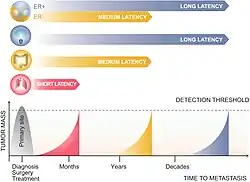

Les métastases font toute la gravité du cancer car l'extirpation chirurgicale complète d'une tumeur cancéreuse ne permet pas d'avoir la certitude qu'une métastase ne se découvrira pas, des mois ou des années plus tard[5].

Par définition, la dormance du cancer est une phase d'arrêt de la progression du cancer qui survient pendant la phase de formation de la tumeur primaire ou après l'invasion de sites secondaires [130]. La dormance métastatique se produit spécifiquement en raison de l'acclimatation retardée des cellules cancéreuses en diffusion vers leurs niches secondaires [131] et affecte des cellules envahissantes uniques. ou des grappes de cancer après circulation.

Chez de nombreux survivants du cancer, les cellules cancéreuses dormantes sont présentes longtemps après l'ablation radicale de la tumeur primitive et seraient responsables de rechutes tardives [131]. Deux mécanismes de dormance existeraient: la dormance angiogénique dans laquelle un équilibre est réalisé entre la division cellulaire et la mort cellulaire par absence de vascularisation des cellules cancéreuses et la dormance à médiation immunitaire dans laquelle la masse tumorale est préservée de la cytotoxicité des cellules immunitaires [132],[13]. Certains pensent que le microenvironnement de l'organe cible ordonne aux cellules tumorales circulantes d'entrer en dormance, tandis que d'autres pensent que les tumeurs primaires précodent une signature de dormance sur les cellules tumorales circulantes qui s'activent lorsque les cellules tumorales circulantes pénètrent dans le microenvironnement hôte. Une autre explication possible est que la dissémination précoce engendre des cellules tumorales circulantes qui répondent aux signaux induisant la dormance et entrent en dormance dans les organes cibles [133].

On peut trouver des cancers métastatiques en même temps que la tumeur primaire, ou bien des mois voire des années plus tard. Quand on trouve une deuxième tumeur chez un patient qui a déjà été traité pour un cancer dans le passé, il s’agit plus souvent d’une métastase que d'une nouvelle tumeur primaire.